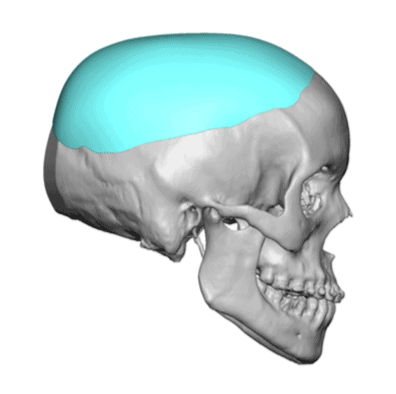

Patient 51

Desire for taller and rounder head shape.

Two stage custom skull implant augmentation technique.

Desire for taller and rounder head shape.

Two stage custom skull implant augmentation technique.